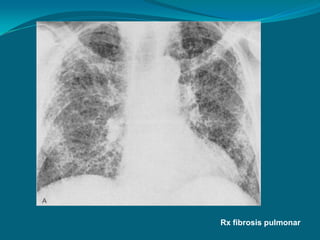

PATRÓN RETICULAR O PULMÓN

EN PANAL

 Se caracteriza por la presencia en el parénquima pulmonar de quistes

de pequeño tamaño (hasta 1 cm) redondeados u ovales, que dan

aspecto de un “panal” y que pueden acompañarse de pérdida de

volumen.

 La presencia de panalización puede significar lesión destructiva final

con fibrosis y distorsión de la arquitectura pulmonar de grado severo.

 Probablemente representa el “estadio final” de gran cantidad de

lesiones infiltrativas (intersticiales).

 Puede estar producido por:

   Fibrosis pulmonar (+ representativa).

   Neumoconiosis.

   Histiocitosis X.

   Colgenosis.

   Neumonías intersticiales.

Rx fibrosis pulmonar

. Radiografía con patrón reticular basal y

periférico muy sugerente de fibrosis pulmonar